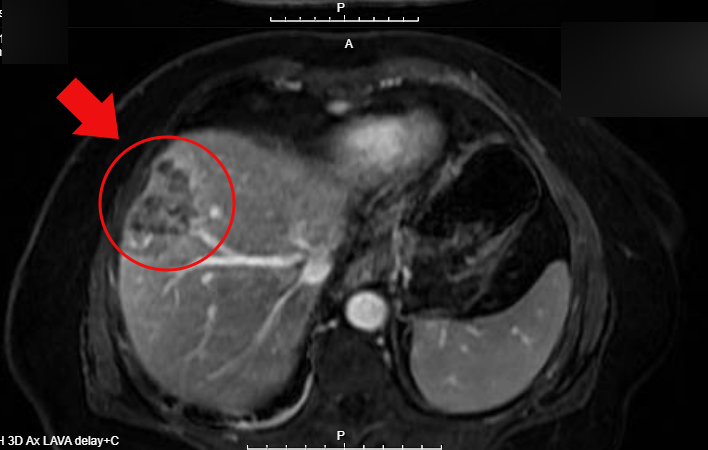

医院急诊科医生曾贤祥接诊后,立即为老人安排CT检查,影像提示肝脏占位性病变,高度怀疑肝脏肿瘤。患者随后转入外科病房,值班医生李嘉豪敏锐意识到病情复杂,为明确诊断,果断进行全腹增强CT检查。结果出乎意料:不仅肝脏有病灶,结肠部位也发现可疑占位。随后的肠镜及活检病理最终确诊——结肠有一个约2厘米的中分化腺癌。

腹腔镜右半结肠癌根治术本身已是高难度手术,同期施行腹腔镜转移性肝癌(肝中叶)切除术,其技术难度呈指数级增加。同时,常规肝癌切除仅需处理单一肝断面,而肝中叶切除则需在同一术中处理多个解剖平面,进出肿瘤的管道系统复杂,肿瘤两侧还紧邻重要血管,需极大程度予以保护。

术中,团队运用腹腔镜超声、荧光腹腔镜及3D腹腔镜等先进技术精准划定切除范围,最终将病灶完整切除;术后,再次腹腔镜超声确认无肿瘤残留,肝脏血运良好,重要血管与胆管无损伤,止血彻底。

凭借精湛的技术与默契的配合,团队实现了结肠原发癌与肝转移瘤的一次性完整切除。术后病理证实了术前MDT判断:肝脏肿瘤同样为中分化腺癌,系结肠癌转移,最大直径达7厘米。